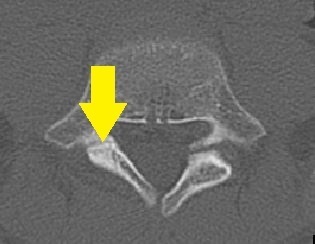

画像検査・診断について

単純レントゲン検査で椎弓・骨年齢の確認、

MRIでは腰椎分離症早期診断を、CT検査(他院依頼)では病期の判定を目的とします。

- 単純レントゲン画像 側面像

- MRI画像

- CT画像

L5左は腰椎分離症終末期